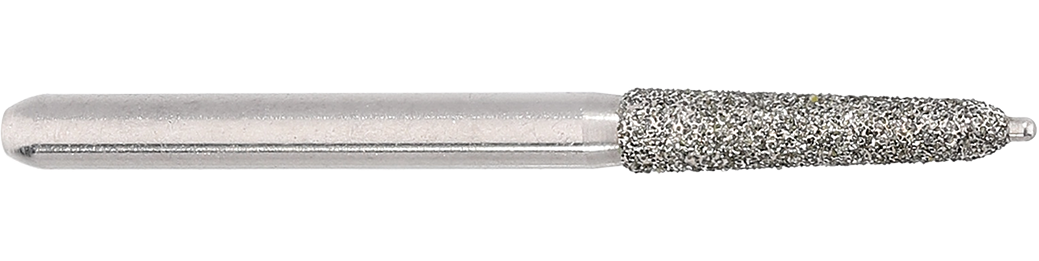

878KP

878KP

SKU: 878KP.314.021.K2 5ER

Tapered chamfer, torpedo - Creates a cutting depth of 0,38 mm (size 018) or 0,54 mm (size 021) at the crown margin

Crown Preparation | Pin-Diamonds Diamond instruments with guide pin for controlled tissue-preserving crown preparation. Advantages: Guide pin as &ldquohorizontal distance keeper&rdquo: For circular material reduction the guide pin guarantees controlled preparation with an even cutting depth. This way a uniform preparation is created, avoiding the &ldquogutter&rdquo effect. Controlled preparation of a defined crown margin. Guide pin as &ldquovertical distance keeper&rdquo: During the preparation of a subgingival margin the 0.5 mm long guide pin assures that a pre-defined distance to the periodontium is kept. Damage to the biological width (the area at the coronal side of the alveolar bone) is largely avoided.